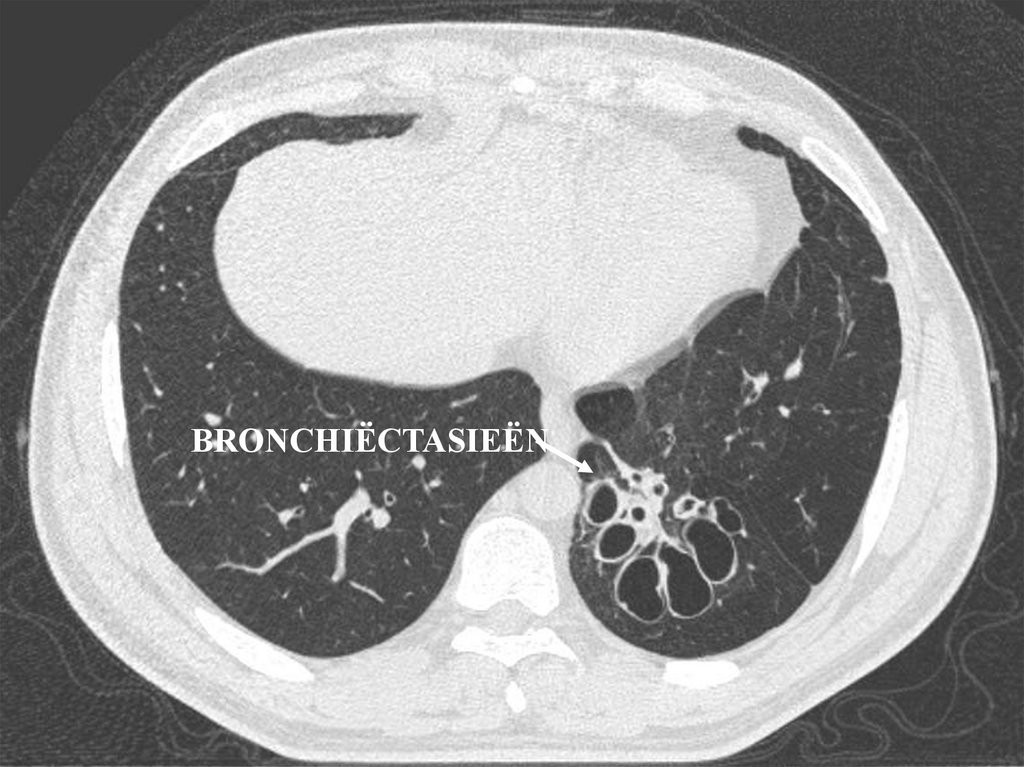

• Bronchiëctasieën

1) Bronchiëctasieën

BRONCHIËCTASIEËN

• Bronchiectasieën

– Bronchiectasieën.

Bronchiëctasie

Vesiculair AG

Grove crepitaties